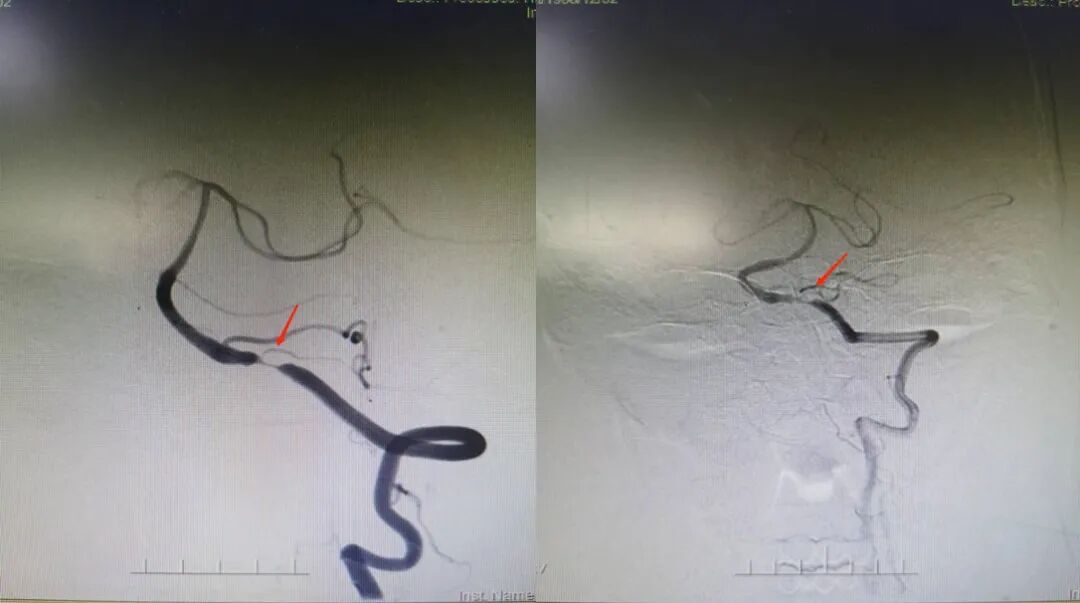

入院影像检查

导丝怎么扩【载药时代 球扩天下】NOVA DES®颅内药物洗脱支架在症状性颅内动脉狭窄中的应用—烟台鲁东医院使用体会二例!_https://www.jmylbn.com_新闻资讯_第19张

重要影像结论:右侧颈内动脉C6段重度狭榨。

重要影像结论:右侧颈内动脉C6重度狭窄(90%)。

诊断

主要诊断:右侧颈内动脉C6段重度度狭窄

病变部位:右侧颈内动脉C6段

远端正常血管直径(mm):3.1

狭窄处最小直径(mm):0.5

病变长度(mm):10

狭窄度(%):90%以上

治疗中影像

导丝怎么扩【载药时代 球扩天下】NOVA DES®颅内药物洗脱支架在症状性颅内动脉狭窄中的应用—烟台鲁东医院使用体会二例!_https://www.jmylbn.com_新闻资讯_第20张

导丝怎么扩【载药时代 球扩天下】NOVA DES®颅内药物洗脱支架在症状性颅内动脉狭窄中的应用—烟台鲁东医院使用体会二例!_https://www.jmylbn.com_新闻资讯_第21张

导丝怎么扩【载药时代 球扩天下】NOVA DES®颅内药物洗脱支架在症状性颅内动脉狭窄中的应用—烟台鲁东医院使用体会二例!_https://www.jmylbn.com_新闻资讯_第22张

导丝怎么扩【载药时代 球扩天下】NOVA DES®颅内药物洗脱支架在症状性颅内动脉狭窄中的应用—烟台鲁东医院使用体会二例!_https://www.jmylbn.com_新闻资讯_第23张

术后影像及检查

影像结论:血管成形良好,支架贴壁良好,远端显影良好。